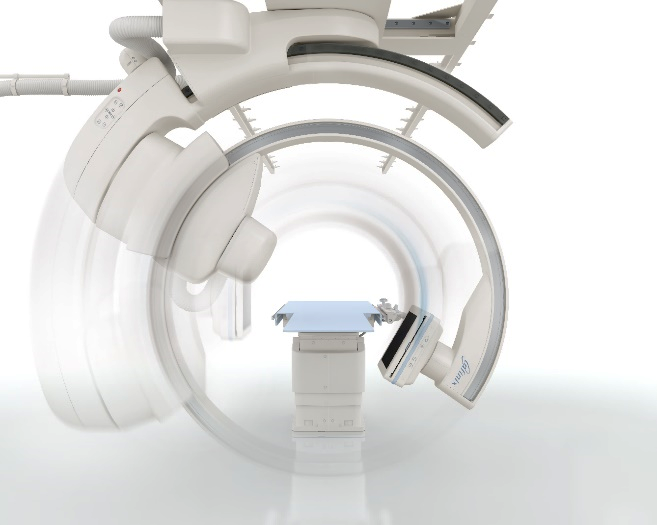

Ангіографічна система з кріпленням на стелі та великим розміром детектора для застосування в ангіографії та інтервенційній радіології, зокрема інтервенційній онкології.

Забезпечуючи неперевершений гнучкий доступ до пацієнта та можливість отримати 3D об’єм від голови до ніг багатоосьова система з кріпленням на стелі ідеально підходить навіть для найскладніших інтервенційних процедур.

Система Alphenix Sky+ має унікальну конструкцію подвійної С-арки, завдяки цьому забезпечується:

Завдяки ізоцентричному обертанню система Alphenix Sky+ забезпечує неперевершений доступ та покриття навіть при найскладніших втручаннях. Подвійна конструкція С-арки з можливістю обертанням як справа, так і зліва від пацієнта з найбільшою швидкістю дозволяє скоротити час затримки дихання, зменшити кількість контрасту та отримати бездоганний 3D об'єм від голови до п’ят без необхідності переміщувати пацієнта: